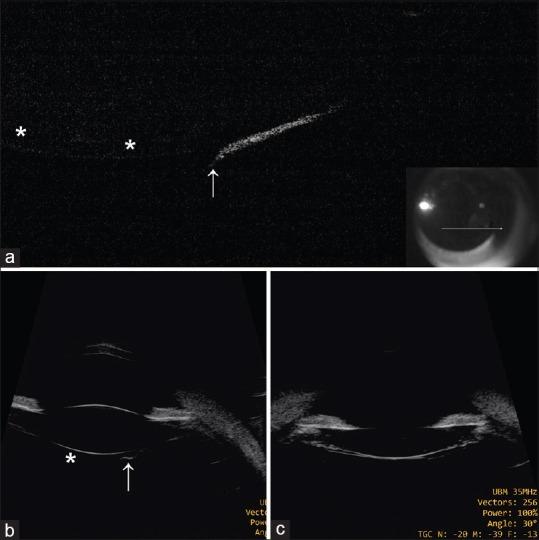

Thin posterior capsule in persistent fetal vasculature causing an appearance of spontaneous posterior capsular rupture.